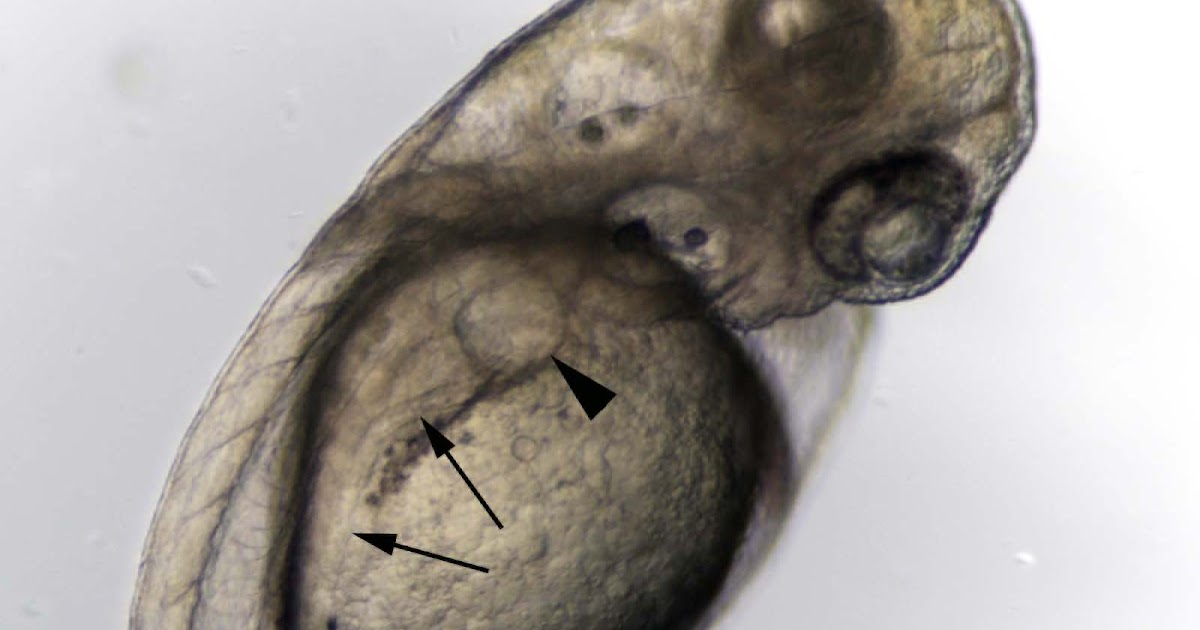

A Possible Zebrafish Model Of Polycystic Kidney Disease: Knockdown Of

zebrafish polycystic kidney wnt5a knockdown kidneys cysts

zebrafish kidney polycystic wnt5a knockdown disease causes kidneys cysts